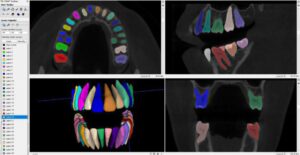

كما تناولت دراسة حديثة بعنوان “تجزئة الأسنان وتصنيفها في الصور المقطعية المحوسبة (CBCT) باستخدام الشبكات العميقة ثلاثية الأبعاد، مما يساهم في تجاوز مشكلات تداخل الجذور وتسهيل التخطيط للجراحات المعقدة وزراعة الأسنان [22].